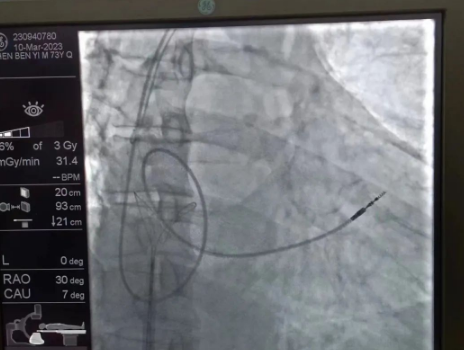

術(shù)中,孫書紅醫(yī)師首先切開起搏器囊袋,游離出起搏器脈沖發(fā)生器,發(fā)現(xiàn)起搏電極完全斷裂,連接于起搏脈沖發(fā)生器,殘端約10cm;考慮患者為起搏依賴患者,需再次植入新的起搏電極導(dǎo)線,穿刺了腋靜脈,放置導(dǎo)絲;同時,李偉杰教授穿刺了左、右股靜脈,于右股靜脈置入了”抓捕器”,左股靜脈備用臨時起搏通路,以防術(shù)中出現(xiàn)心跳驟停。為了準確抓捕到心房內(nèi)的在逃起搏電極,李偉杰教授將導(dǎo)管室的X光機球管調(diào)整成了冠脈模式,這就意味著在抓捕過程中,醫(yī)生要比平時的手術(shù)“吃”更多射線……

在透視模式下,抓捕全憑醫(yī)生的經(jīng)驗與手感,一次次嘗試,一次次失敗,在場外觀摩手術(shù)的醫(yī)生同樣為李偉杰教授捏了一把汗,“找到了!”電子屏里抓捕器向在逃起搏電極“發(fā)起進攻”,一把逮住并順利拔出一根長達58cm的起搏電極。